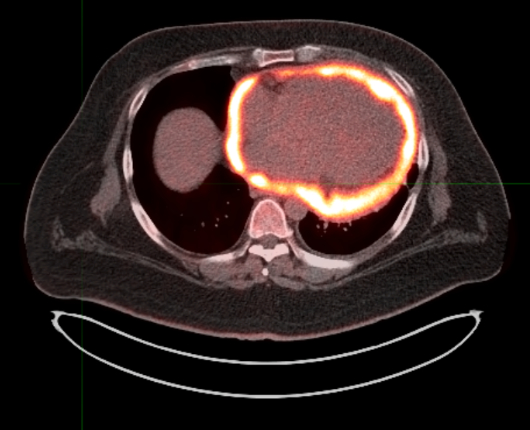

A 33-year-old man with no medical history or environment exposures, presented with dyspnea, nausea, and vomiting. He was tachycardic, with jugular venous distension, pulsus paradoxus, low voltage QRS and echocardiogram (TTE) showed a large pericardial effusion with ventricular interdependence. He underwent pericardiocentesis with negative fluid studies, including cytology. Two months later he represented with dyspnea and pleuritic chest pain, was diagnosed with pericarditis, and found to have recurrent pericardial effusion without tamponade. He was treated with aspirin and colchicine and discharged, with surveillance TTE showing a stable pericardial effusion but with significant adhesions and constrictive physiology (confirmed on right heart catheterization). Negative QuantiFERON was obtained and Anakinra started. Two months later he remained symptomatic with new pleural effusions and was sent for positron emission tomography scan which revealed diffuse intensely hypermetabolic pericardial thickening/fluid, up to 3.8 cm in maximal thickness and increased uptake in mediastinal nodes. Next, a cardiac MRI showed extensive circumferential thickening of the pericardial space approximately 2.5 cm in thickness. Both the visceral and parietal pericardium exhibited extensive scattered delayed hyperenhancement. Subsequent pericardial biopsy showed markedly fibrotic pericardium and pathology showed biphasic malignant pericardial mesothelioma. Immunosuppressive medications were stopped, and he underwent thoracentesis. After multidisciplinary discussions, he was started on nivolumab every two weeks and ipilimumab with a plan for surgery based on response to therapy. However, progressive symptoms and worsening constriction physiology led to palliative consultation and comfort care transition, with him dying shortly after.